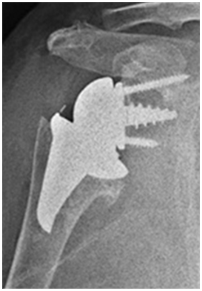

- 인공관절수술 후

수술적 치료

회전근개파열 복원 수술

정형외과 교과서에서 이야기 하는 수술이 필요한경우

- 젊은 나이에 외상후에 어깨 기능이 갑자기 악회된 경우

- 1년 이상 비수술적치료의 효과가 없는 경우

- 파열의 크기가 1~2cm 이상일 경우

- 극하근이 파열된 경우